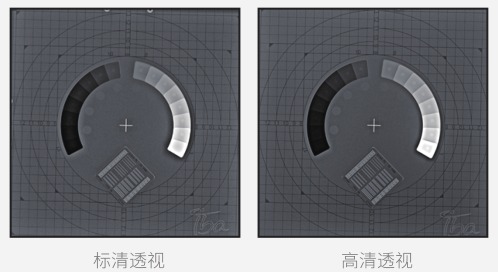

● 标清透视

以较少的辐射剂量呈现医生所需的诊断图像,为临床初筛提供优质影像。

● 高清透视

在初诊筛查的基础上,使用高清透视功能辅助医生再次确认病灶点,降低漏诊、误诊的概率。

● 高清点片

在透视检查下,可进行毫秒级高清点片,准确捕捉病灶,为医生提供高清的诊断依据。